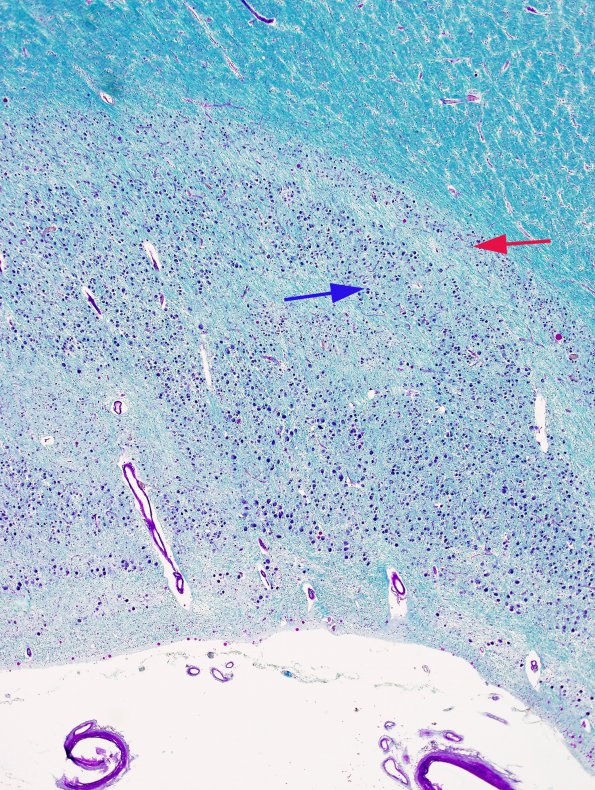

Washington University Experience | BASIC PROCESSES | Transneuronal Degeneration | 2B2 Transneuronal degeneration (LGN) (Case 2) layers 1-6 LFB-PAS 1

Laminae of neurons are separated by layers of white matter and, as a result, use of LFB-PAS stain better shows the laminae seen in two areas of the LGN. Neurons at the red arrow are atrophic and those in the blue arrow area are better preserved in size and number (LFB-PAS).